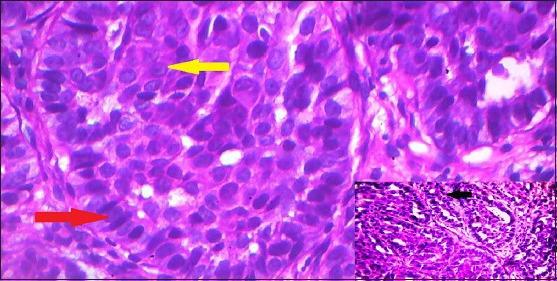

Basaloid squamous cell carcinoma (BSCC) is a distinct variant of conventional squamous cell carcinoma (SCC), predominantly localized in the upper aerodigestive tract. In the head and neck region, the tumor has a strong predilection for extra-laryngeal sites, such as the base of the tongue, tonsil, hypopharynx and supraglottic larynx. BSCC has well-defined histological features, characterized by nesting, lobular and trabecular arrangement of basaloid cells. Central comedonecrosis within the cell nests, cells with nuclear palisading and high-grade dysplasia in overlying mucosa are the main characteristics. The tumor is considered to be highly aggressive and often presents itself as an advanced stage lesion, thus demanding early diagnosis and prompt treatment. We here report a case of 72-year-old male diagnosed with BSCC involving the right tonsillar region.

基底样鳞状细胞癌(BSCC)是传统鳞状细胞癌(SCC)的一种独特变体,主要位于上消化道。在头颈部区域,该肿瘤强烈倾向于喉外部位,如舌根、扁桃体、下咽和声门上喉。BSCC具有明确的组织学特征,其特点是基底样细胞呈巢状、小叶状和小梁状排列。细胞巢内的中央粉刺样坏死、细胞核呈栅栏状排列的细胞以及覆盖黏膜的高级别发育异常是主要特征。该肿瘤被认为具有高度侵袭性,常表现为晚期病变,因此需要早期诊断和及时治疗。我们在此报告一例72岁男性被诊断为累及右侧扁桃体区域的基底样鳞状细胞癌。